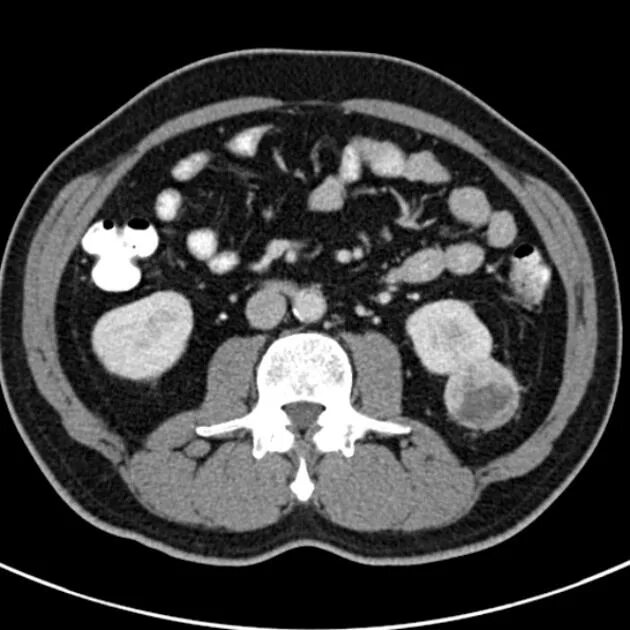

Bosniak классификация кт